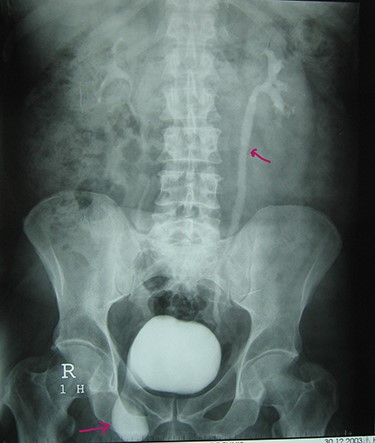

A 72-year-old man with a history of controlled diabetes and hypertension presented to our department with right inguinal swelling and intermittent lower urinary tract symptoms (LUTS) with pollakiuria, dysuria, prolonged micturition time and a sensation of a full bladder after micturition. He reported nausea, vomiting and right lower quadrant paint. The patient also reported having to manually compress the scrotum in order to empty the bladder. Physical examination revealed a slightly painful on palpation and reducible 6 cm right inguinal hernia extending into the right hemiscrotum. The body mass index of the patient was 31.4 kg/m2. His PSA was 4.3 ng/ml. On uroflowmetry, maximum flow rate (Qmax) was 13 ml/s and the voided volume was 180 cc. The uroflow curve was flat. The Bacteriological examination of urine was negative. Retrograde urethrocystography revealed right inguinal hernia containing a portion of the urinary bladder (Figs 1,2). He also had an intravenous urography in order to study the upper urinary tract and to have an idea of the renal function. This radiological exploration confirms the data of the retrograde urethrocystography and illustrates well the bladder hernia. However, a moderate left hydronephrosis with a nonobstructive pyelic calculus of 1.5 cm was observed on intravenous urography (Figs 3,4). Intraoperative findings revealed a direct right inguinal hernia with complete herniation of bladder into the scrotum. The bladder appeared healthy with no signs of injury and was restored to its normal anatomical position without resection. The hernia was repaired with a biologic mesh by the Lichtenstein technique. The patient had an uneventful postoperative course. Concerning his pyelic calculus problem, shock wave lithotripsy sessions were scheduled.

Urethrocystography: no obstruction under the bladder in the per mictional image.